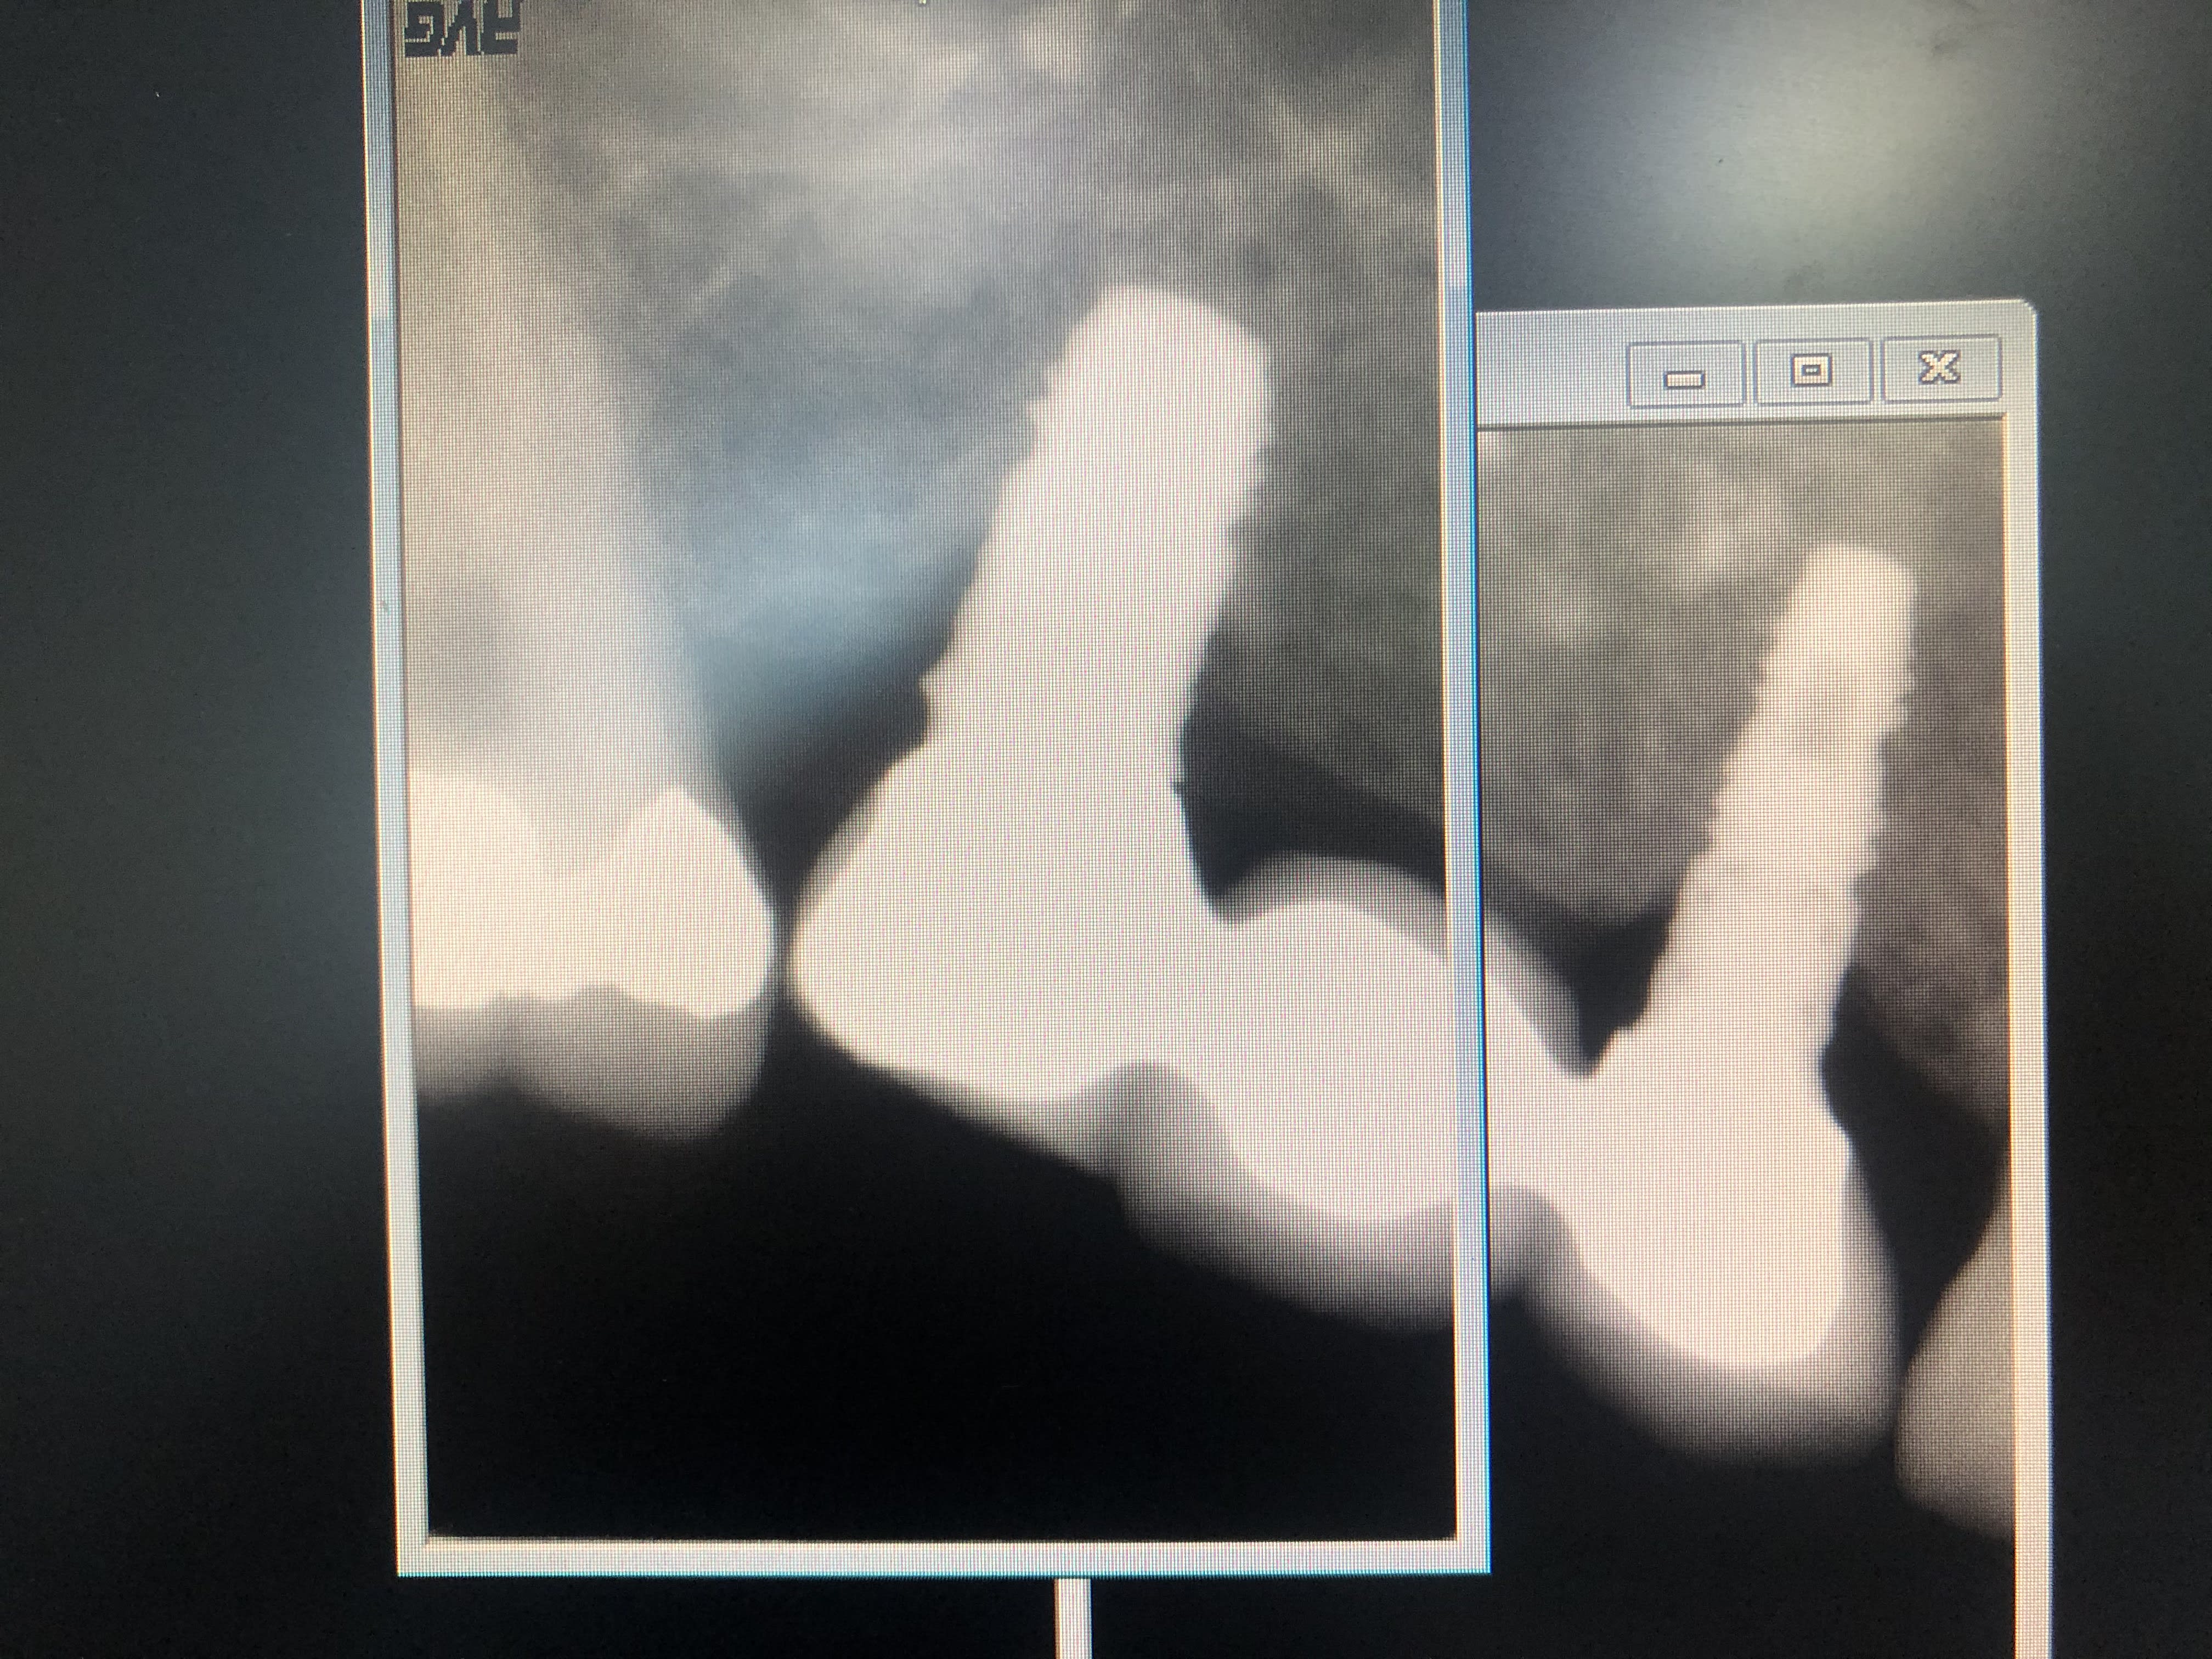

Bjr, j'ai besoin d'un coup de pouce pour m'identifier les implants du bridge en secteur 1.

factoche, Frialit

https://www.spotimplant.com/fr/implants-dentaire/friadent/frialit-2